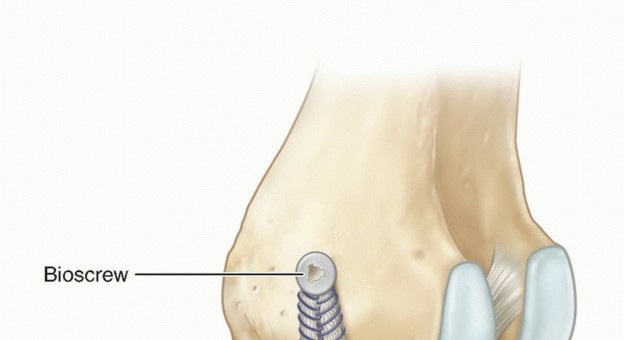

The distal tibial fixation has to reconstruct the anterior and posterior aspect of the native MCL (TECH FIG 4).

- TECH FIG 4 • Double-bundle MCL allograft reconstruction technique using bioabsorbable screw fixation. (Courtesy of Mark D. Miller, MD.)

The allograft can be anchored anteriorly and posteriorly along the anatomic attachment sites using an interference screw (as depicted), a screw and washer, or a staple. - Distal Fixation in Chronic Injuries

The MCL and POL grafts fixed first on the tibial side with 7- × 25-mm bioabsorbable screws (TECH FIG 6H)

of MCL (black arrow), tibial insertion of the central arm of the POL (blue arrow), femoral insertion of MCL (green arrow), femoral insertion of the central arm of the POL (yellow arrow), and superficial MCL (red star). Semimembranosus being retracted inferiorly to reveal tibial insertion of POL. G. Two semitendinosus or tibialis tendon allografts are cut to 16 cm for the MCL, 12 cm for the POL. H. MCL and POL grafts fixed first on the tibial side with 7- × 25-mm bioabsorbable screws. I-K. Grafts fixed with 7- × 25-mm bioabsorbable screws on the femoral side, with completed reconstruction. (B,F-K: Courtesy of Charles H. Brown, Jr., MD.)

MCL tensioned at 30 degrees, neutral tibial rotation, POL tensioned at full extension Grafts fixed with 7- × 25-mm bioabsorbable screws on the femoral side (TECH FIG 6I-K)